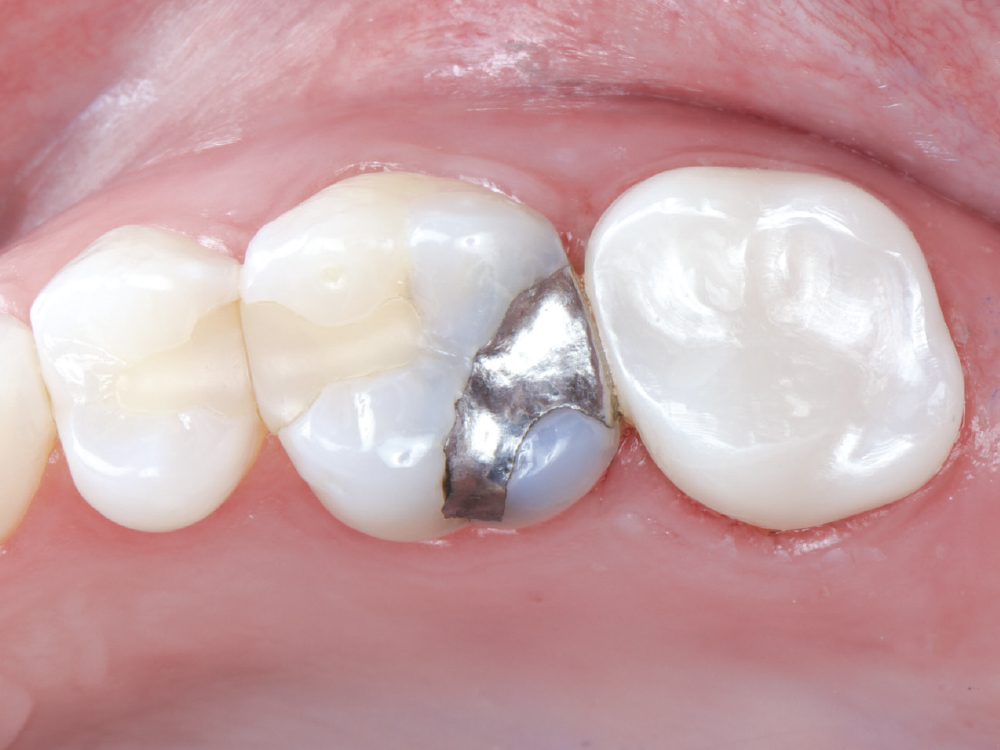

The patient’s chief concern was an open mesial margin of the crown on tooth #15

Figure 1: The patient’s chief concern was an open mesial margin of the crown on tooth #15, which was causing gingival inflammation and shredding her dental floss.

The crown was a 20-year-old Captek™ PFG high-noble bilayered restoration

Figure 2: The crown was a 20-year-old Captek PFG high-noble bilayered restoration.